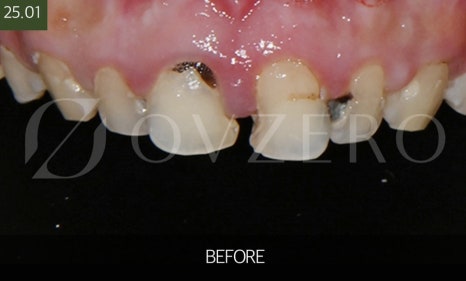

Situations Where Zirconia Crowns Are Needed

A zirconia crown is a treatment chosen

when a tooth needs to be “protected overall.”

For example, if a cavity has progressed significantly

and a resin or inlay is not strong enough,

if a tooth is chipped or cracked and pain keeps recurring while chewing,

or if a tooth has been weakened after root canal treatment,

crown treatment is usually performed.